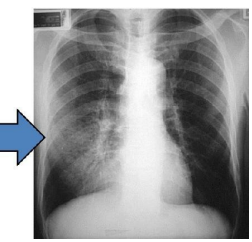

Acute Respiratory Distress Syndrome

A form of diffuse alveolar injury. It is characterized

by increased permeability of the alveolar-capillary barrier, leading to an influx of fluid into the alveolar space.

This results in hypoxemia and pulmonary hypertension, which further contributes to the V/Q mismatch